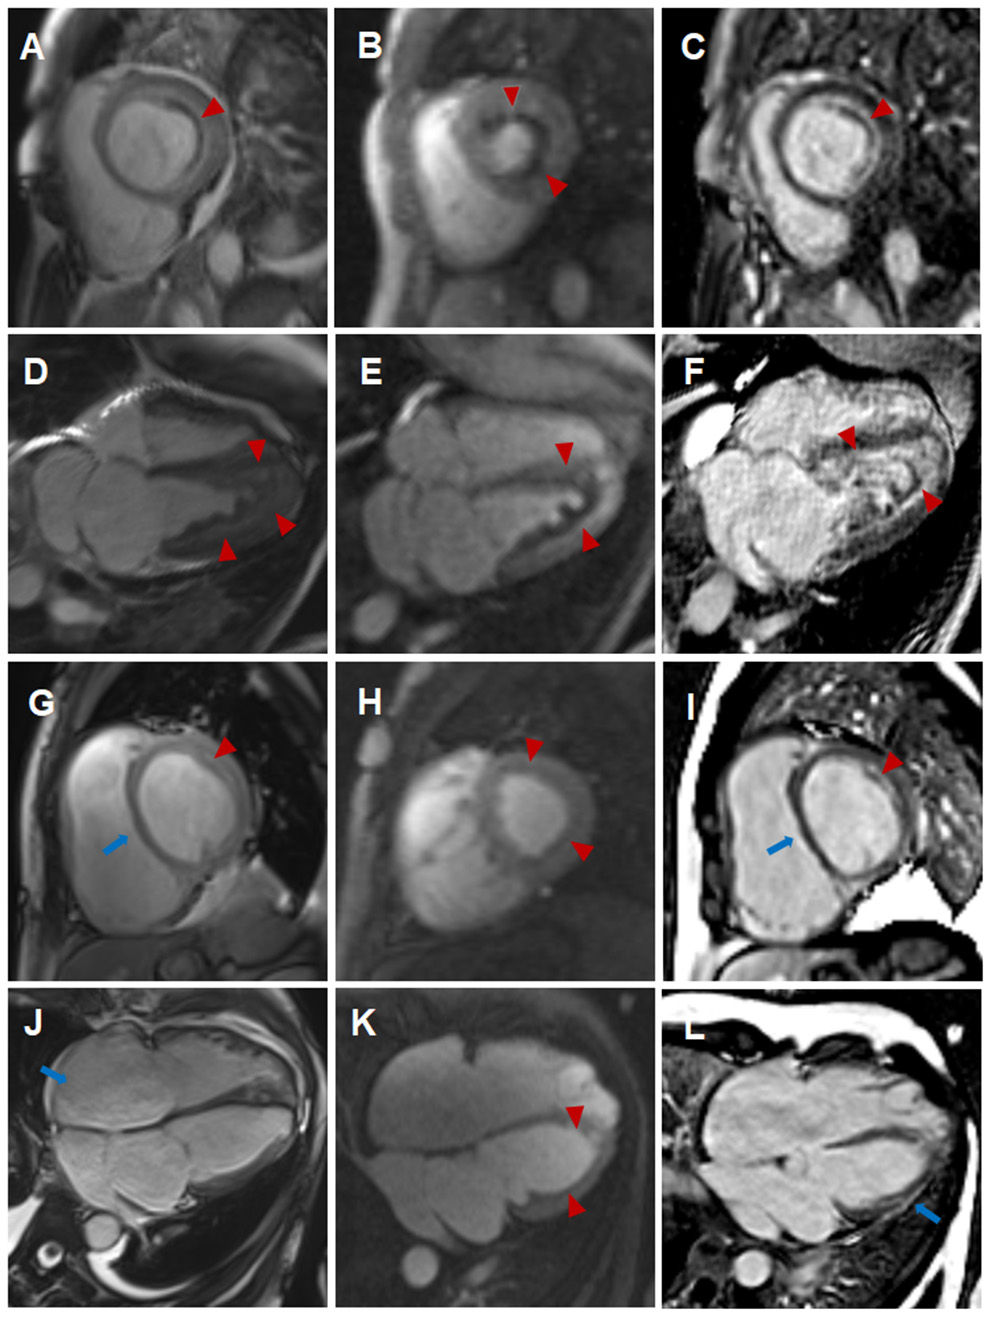

Figure 2

Comparison of cardiovascular involvement detected by CMR during two separate hospitalizations (A–F) CMR findings during the initial hospitalization (A–C, short-axis view; D–F, four-chamber view). Distinct high-signal-intensity plane separating the thrombus from underlying myocardium on end-diastolic cine images (A,D, triangular arrows), endocardial surface hypoperfusion zone on perfusion images (B,E, triangular arrows) and endocardial enhancement and overlying non-enhancing thrombus on LGE images (C,F, triangular arrows). (G–L) CMR findings during the subsequent hospitalization (G–I, short-axis view; J–L, four-chamber view). Enlargement of right atrium and right ventricle, flat ventricular septum (G,J, long arrows) and significantly reduced high-signal-intensity plane and thrombus (G,J, triangular arrows) on cine images, significantly reduced endocardial surface hypoperfusion zone on perfusion images (H,K, triangular arrows) and significantly thinning endocardial enhancement and overlying thrombus (I,L, triangular arrows), new strip-like LGE in the lateral wall (L, long arrows) on LGE images, representing replacement fibrosis.

Eosinophils reduced to normal (Table 1) and her symptoms gradually improved after treatment according to the 2015 EGPA Consensus Task Force recommendations (4). Chest CT showed that the diffuse lesions of both lungs were absorbed, and the pleural effusion was reduced after the treatment. Unfortunately, the patient was readmitted for dyspnea, bilateral lower limb edema and systemic ecchymosis after 10 months. Transthoracic echocardiography showed deposits in the mural LV endocardium were significantly reduced, the LV diameter returned to normal but greater diameter of right atrium (RA) and right ventricle (RV) with moderate-to-severe regurgitation of tricuspid valve and pulmonary valve, severe pulmonary hypertension (eSPAP was 71 mmHg). CMR imaging was performed again, showing enlargement of RA and RV (Table 2, Figure 2J, Supplementary Videos 9–12), significantly improved endocardial enhancement and overlying thrombus on cine, perfusion and LGE images (Figures 2G–L, Supplementary Videos 7–12), remarkably reduced RV systolic function but improvement of LV systolic function (Table 2, Supplementary Videos 7–10), new strip-like LGE in the lateral wall (Figure 2L), representing replacement fibrosis and increased diameters of pulmonary trunk from 28 mm to 32 mm (Figures 1B,F). Multiple lesions of both lungs were significantly absorbed (Figures 1E,F) and encephalomalacia were formed (Figure 1G). Despite the patient received intensive immunosuppressive treatment combing glucocorticoid and immunosuppressant (cyclophosphamide) and aggressive anti-heart failure therapy, the symptoms of right-sided heart failure were not completely relieved and sudden cardiac death occurred 6 months after hospital discharge.

A 44-year-old female patient presented to our hospital with a 1-month history of dizziness, fatigue, chest tightness, and shortness of breath. She also had ecchymosis of the lower legs. The patient presented with a 10-year history of asthma, sinusitis, and nasal polyps (Figure 1D). Electrocardiograph (ECG) demonstrated QS waves in leads V2-V3, ST segment depression in leads V5-V6, and T-wave inversion. Blood pressure was 90/62 mmHg, pulse was 112 beats/minute. Laboratory findings (Table 1) showed increase in the percentage of eosinophils (47.8%), erythrocyte sedimentation rate (ESR) (32 mm/H), C-Reactive protein (CRP) (24.70 mg/L), N-terminal pro-B-type natriuretic peptide (NT-proBNP) (12,045 pg/mL), and troponin I (1.760 ng/mL). Diagnostic work up revealed negative anti-nuclear antibodies (ANA), ANCA, anti-MPO antibodies, and rheumatoid factor. The patient's renal function was normal and there was no evidence of blood infection. Diffusion-weighted imaging of the brain magnetic resonance imaging (MRI) revealed multiple acute cerebral infarctions (Figure 1C) with no obvious cerebrovascular stenosis on magnetic resonance angiography (MRA) (Figure 1H). Chest CT and Cardiac magnetic resonance (CMR) localizing images showed multiple patchy consolidations of both lungs and bilateral pleural effusion (Figures 1A,B). After completing a series of examinations and multi-disciplinary discussions, the patient met the inclusion criteria of the American College of Rheumatology 1990 criteria for the classification of EGPA (3). Transthoracic echocardiography showed numerous deposits in the mural left ventricular (LV) endocardium, obliteration of the apical portion of the left ventricle, enlarged left atrium, moderate pulmonary hypertension [the estimated systolic pulmonary artery pressure (eSPAP) was 46 mmHg] and a small pericardial effusion. 18F-FDG PET-CT showed accumulation of FDG in the lungs and myocardium. CMR was used to assess the cardiovascular involvement which was performed on a 3.0 T MRI at 8 days after admission, confirming Löffler endocarditis (endocardial thickening, edema and enhancement) with LV thrombus on cine, perfusion, and LGE images (Figures 2A–F, Supplementary Videos 1–6), LV volume enlargement and mildly reduced LV systolic function, normal right ventricular volume, and function (Table 2, Supplementary Videos 1–4).